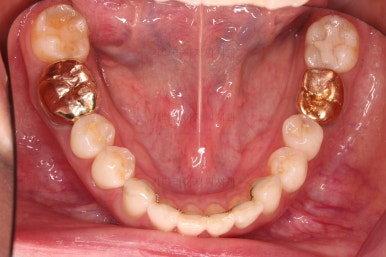

아랫니 부분교정이 끝났고요.

어금니도 원위치로 많이 갔네요.

아랫니 부분교정과 어금니 부분교정은 비교적 조기에 끝났으나(7개월) 임플란트가 생각보다 오래 걸렸습니다.

적절한 공간 확보 이후 해당 부분의 뼈가 너무 얇아 임플란트를 하기에 부적절했던거죠.

치료 종료시의 모습인데요.

임플란트가 잘 들어갔고 아래 앞니도 원하는 모습으로 잘 배열이 되었습니다.